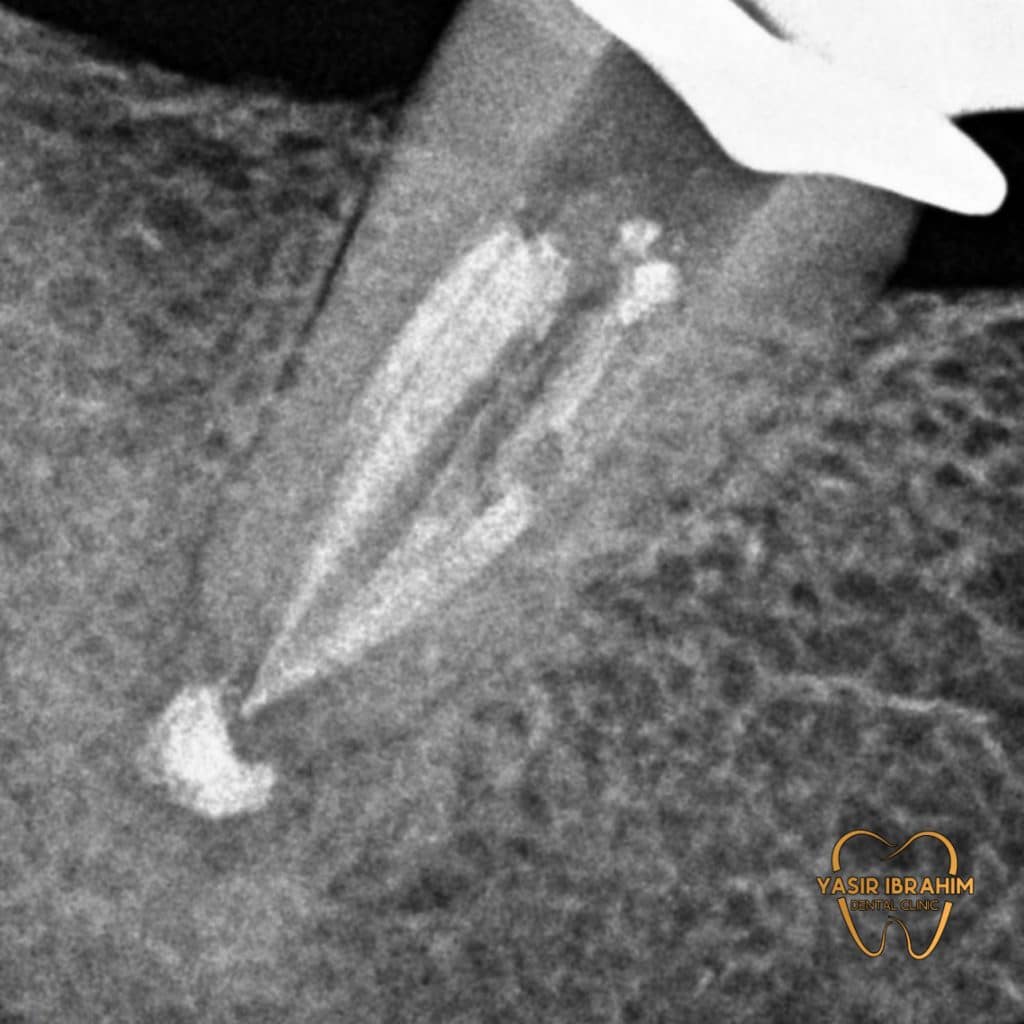

Radiographic analysis show periapical lesion With poor RCT .

2_endo-retretment and doing bio_obturation by MTA .

obturation with MTA.

we notice healing of the periapical lesion by 75% With

disappearance of all symptoms, after one month of obturation by MTA.